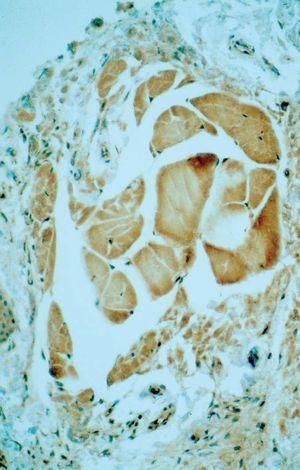

Fig. 5.--Tinción positiva del material coloide con SAP (sustancia P amiloide).